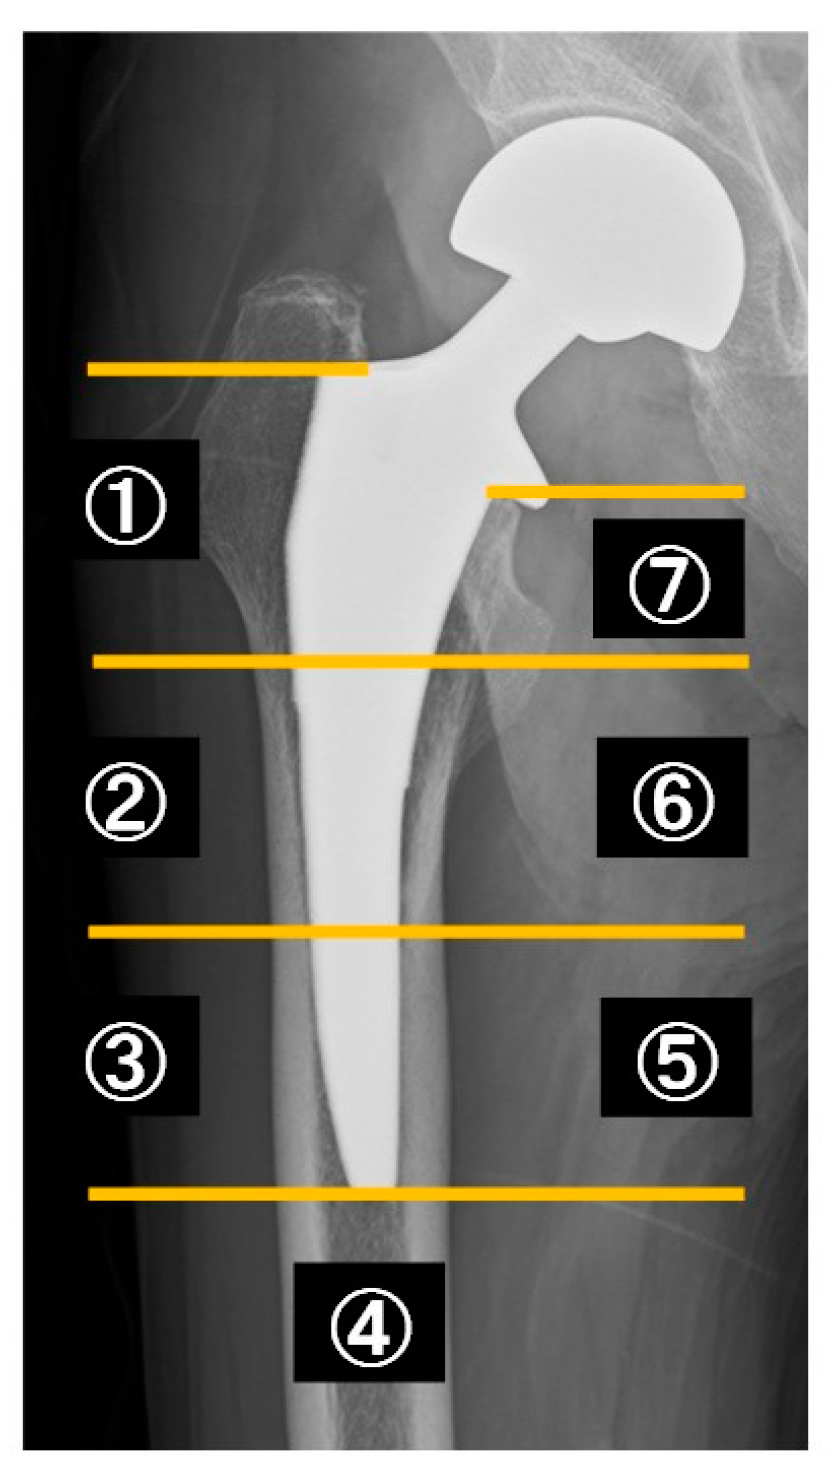

- Gruen, T.A.; McNeice, G.M.; Amstutz, H.C. “Modes of failure” of cemented stem-type femoral components: A radiographic analysis of loosening. Clin. Orthop. Relat. Res. 1979, 141, 17–27. [Google Scholar] [CrossRef]

- Kilgus, D.; Shimaoka, E.; Tipton, J.; Eberle, R. Dual-energy X-Ray absorptiometry measurement of bone mineral density around porous-coated cementless femoral implants. Methods and preliminary results. J. Bone Jt. Surgery. Br. Vol. 1993, 75-B, 279–287. [Google Scholar] [CrossRef] [PubMed]